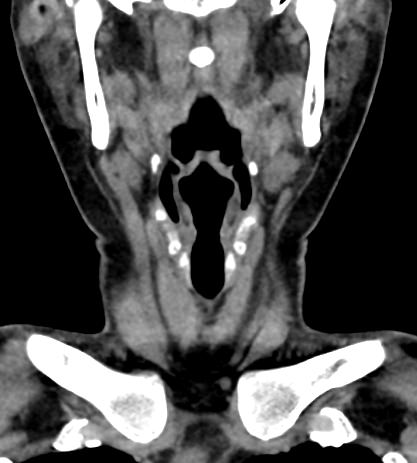

Компьютерная томография является современным высокотехнологичным методом диагностики заболеваний щитовидной железы, основанном на использовании рентгеновского излучения. Процедура отличается быстротой, безболезненностью и проводится без нарушения целостности кожи и расположенных под ней тканей.

В наших центрах обследование щитовидной железы выполняется на современных мультиспиральных томографах TOSHIBA AQUILION, оснащенных увеличенным количеством сверхчувствительных детекторов, позволяющих производить 64 или 128 срезов с минимальной толщиной от 0,5 мм.

Инновационные возможности аппаратов обеспечивают получение множества послойных снимков высокого качества и построение на их основе трехмерной модели органа. Кроме того, аппаратура позволяет за счет сокращения времени сканирования минимизировать лучевую нагрузку на пациента.

КТ щитовидной железы часто используется в диагностике доброкачественных и злокачественных опухолей железы, оценки распространенности процесса, поэтому для улучшения визуализации патологических очагов дополнительно применяется внутривенное болюсное контрастирование. Методика контрастирования позволяет увидеть на снимке опухоли минимальных размеров за счет того, что контраст избирательно накапливается в измененных тканях и обеспечивает яркое изображение патологического очага на фоне здоровых окружающих тканей.

Контрастирование дает возможность определить врачу границы опухоли, ее размеры, степень васкуляризации, точное расположение, особенно это важно при нетипичной (загрудинной) локализации органа.